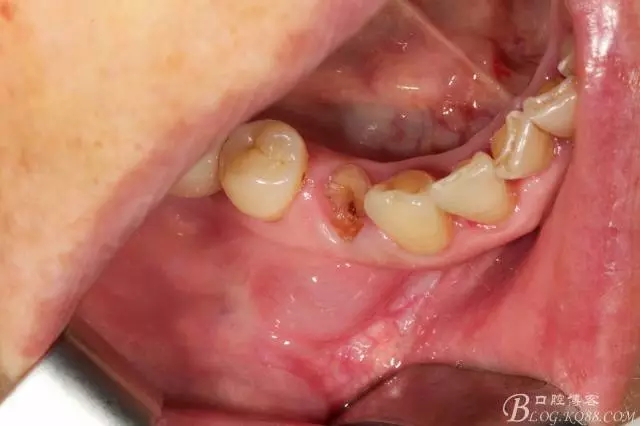

44號牙位術(shù)前照片

拔牙 當(dāng)然這種手術(shù)我必須不翻瓣零翻瓣